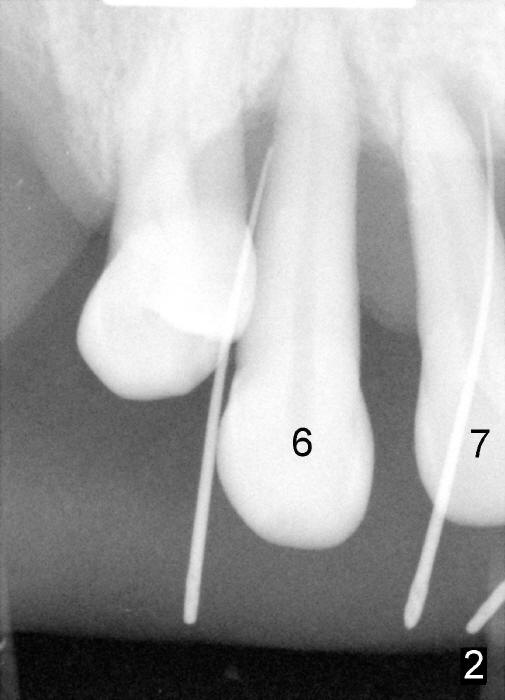

A 52-year-old man has severe periodontal disease (Fig.1-3). It appears that the upper teeth are non salvageable and are best treated by hybrid denture. But his finance is strained.

The most severely affected teeth (#6,7 and 9) are extracted and immediately replaced by 4x20 mm (#7) and 5x20 (#6,9) implants (Fig.4,5). Straight (0 degree) uniposts (3 and 4 mm, respectively) are rotated tightly into the wells of the implants by hand screw driver. In order to have reversibility to hybrid denture in the future, these uniposts are not cemented. Heavy retention grooves are placed between the uniposts and implants. Provisionals are fabricated immediately and cemented temporarily. To increase stability, flowable composite is added to the area between the provisionals of #6 and 7.